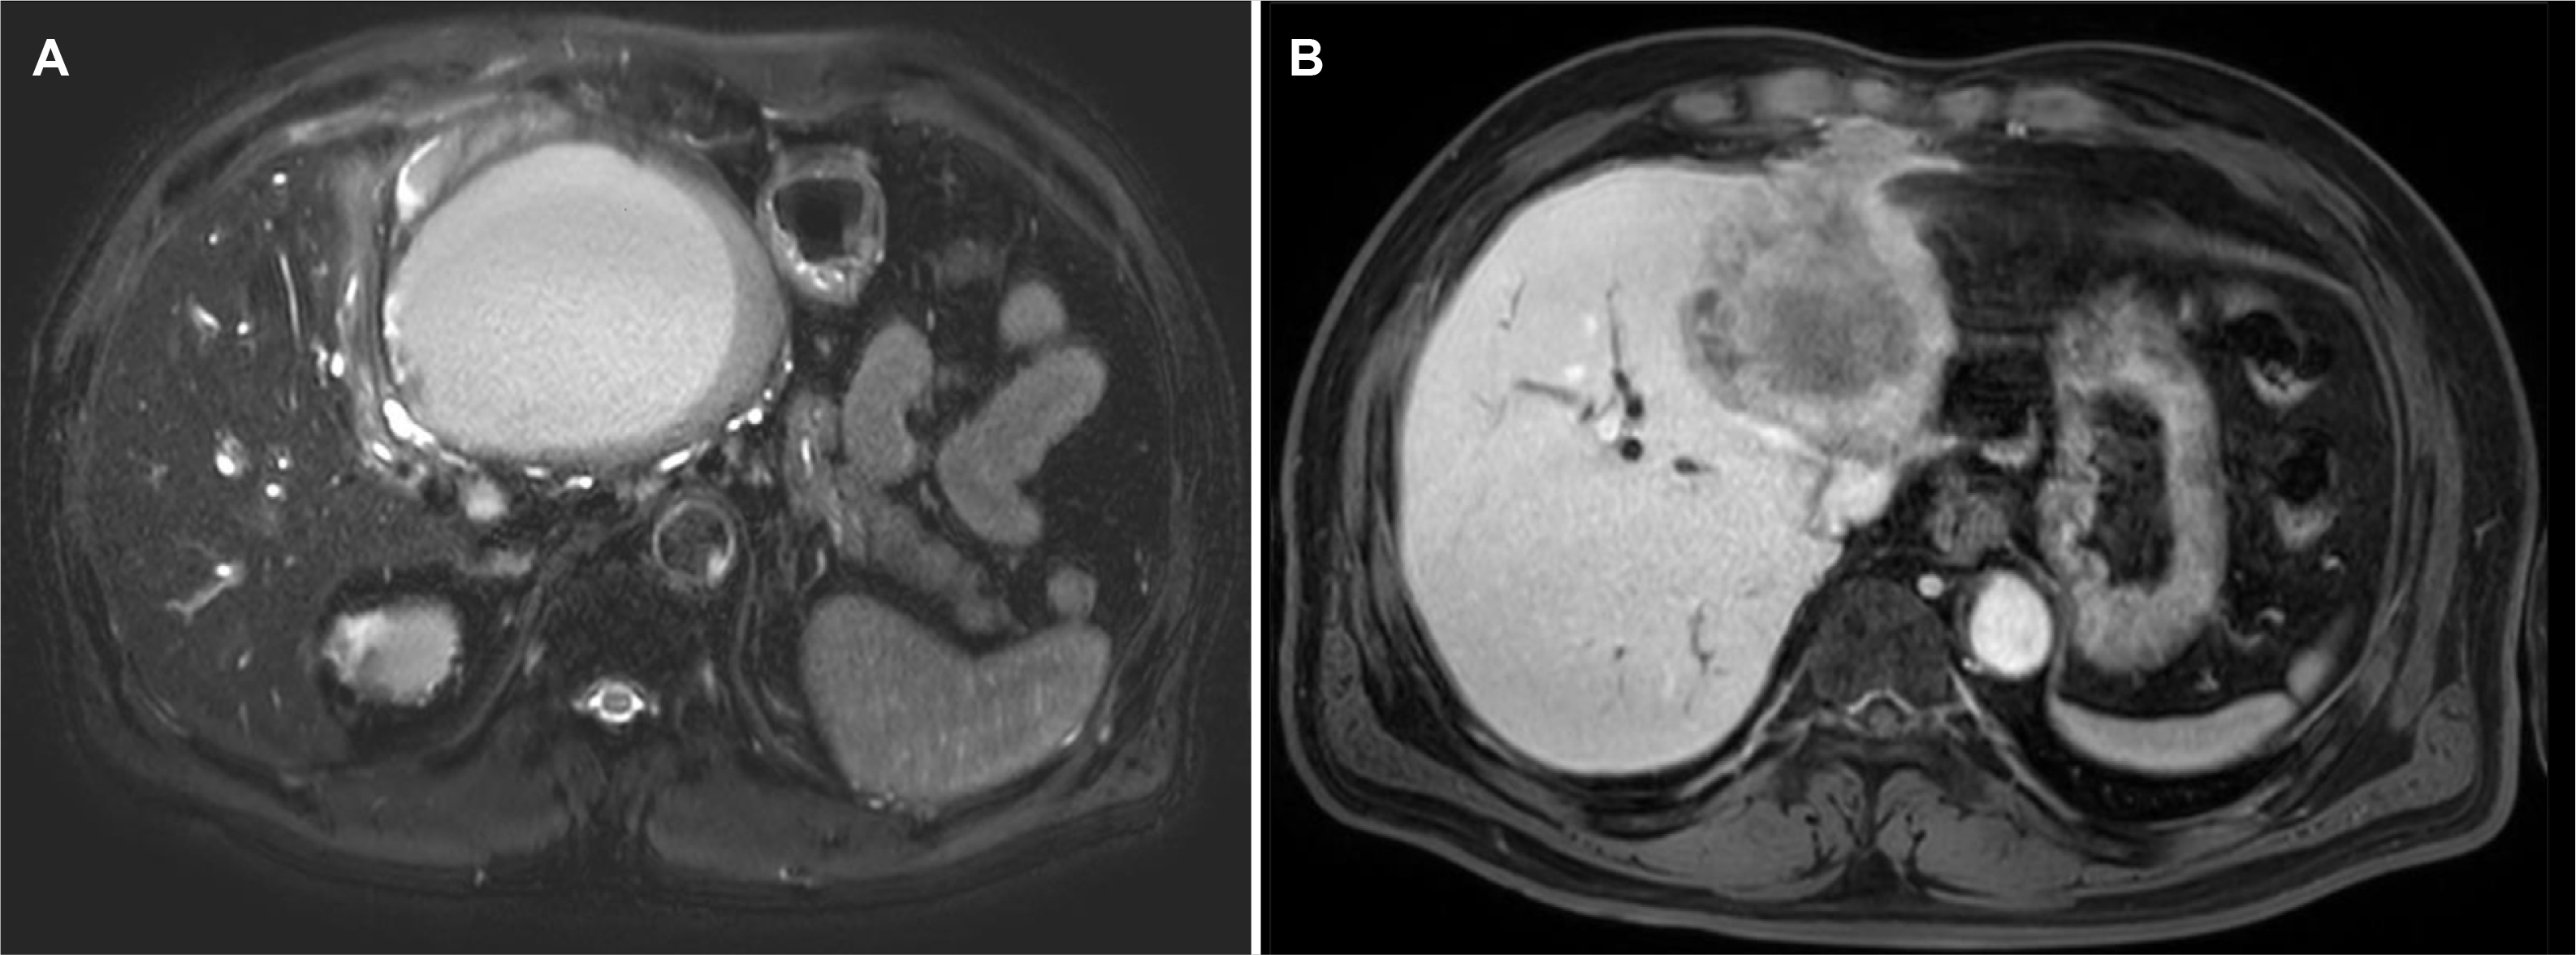

Fig. 3

(A) Magnetic resonance imaging (MRI) T2-weighted images showing a 12 cm high-signal lesion in the left lobe, which was presumed to be an abscess, with associated bilateral intrahepatic duct dilatation. (B) MRI T1 mDIXON portal phase revealed LI-RADS M, indicating definite or probable malignancy not specific to hepatocellular carcinoma.